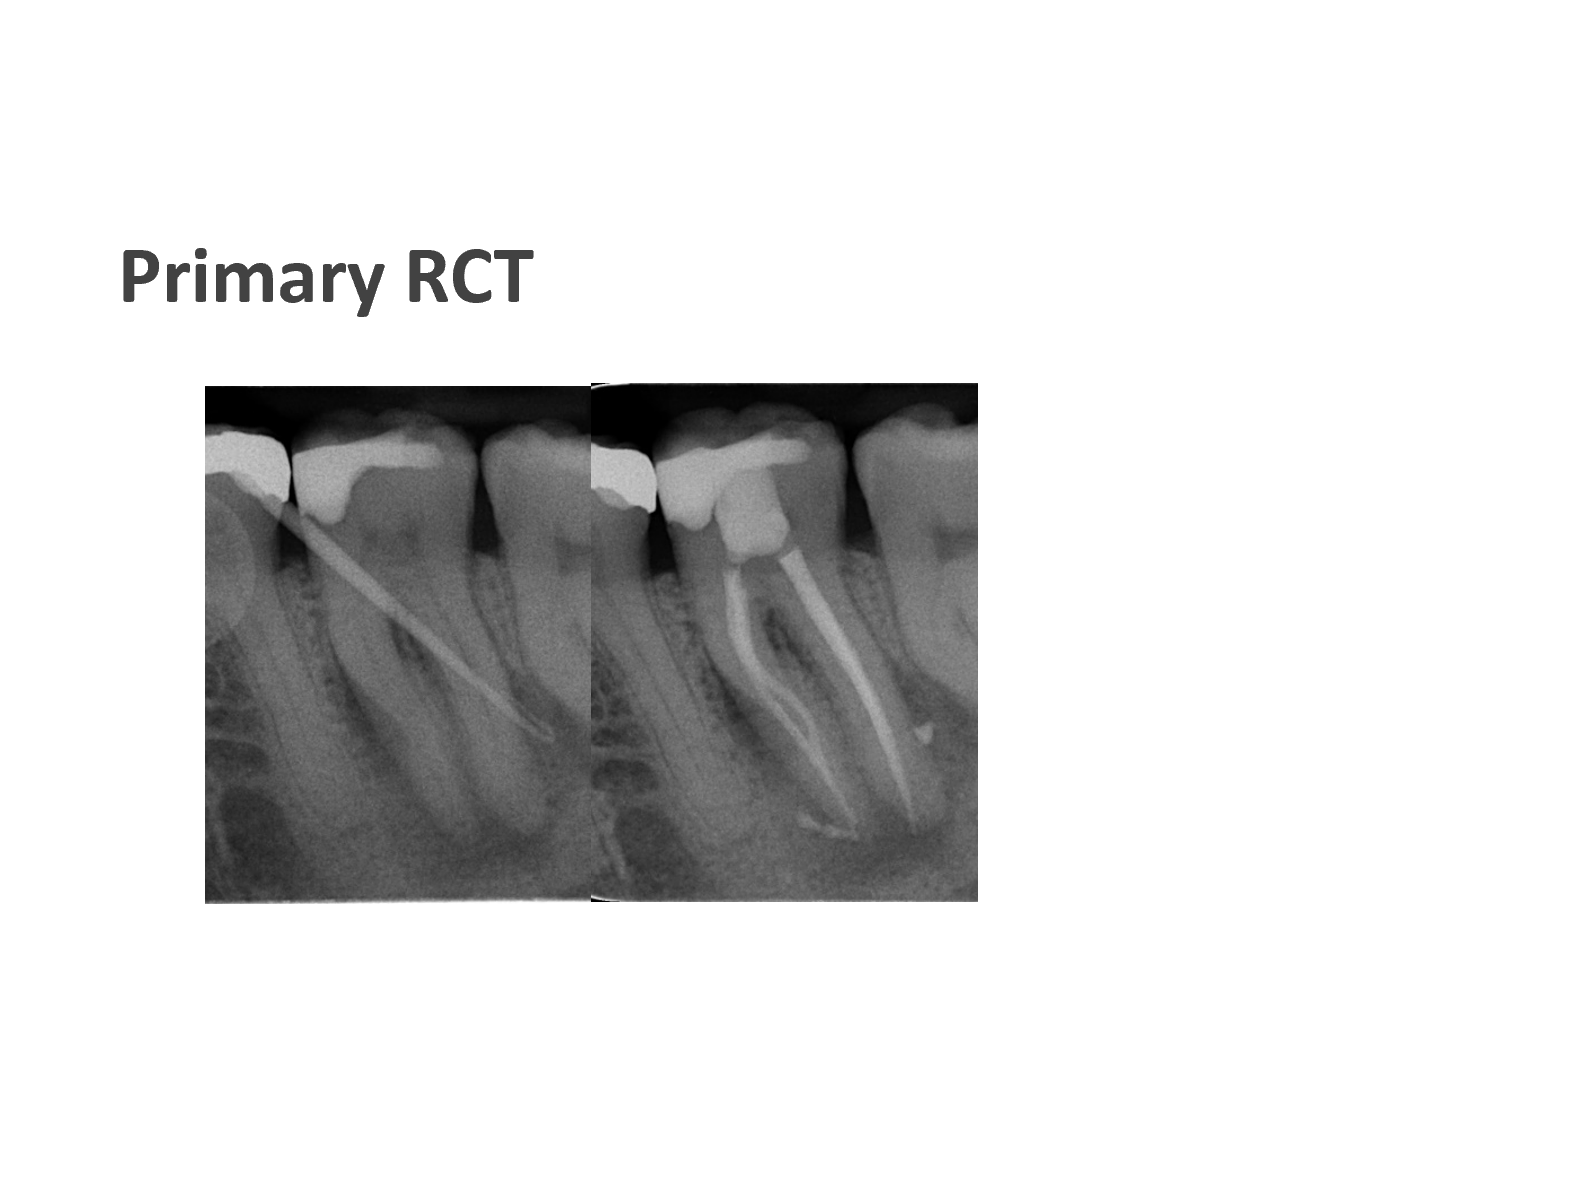

We take pride in providing the highest standard of care at ICE and believe that only the best is good enough for our patients. As such, Shakil completes all endodontic procedures using a state-of-the-art dental microscope. We accept referrals for consultations, root canal treatment (primary and retreatment), management of endodontic emergencies, dentoalveolar trauma and we are also happy to provide definitive restorations as required.